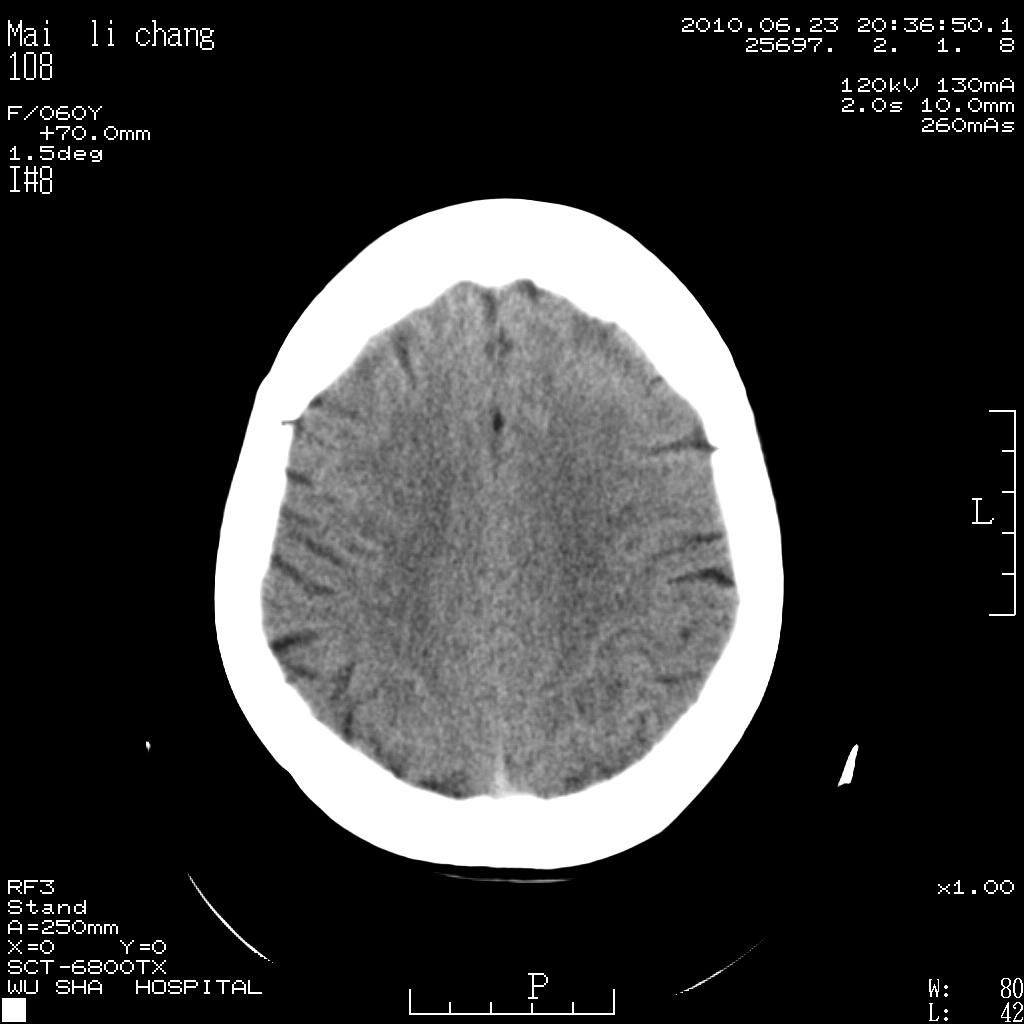

女性,60岁,右手无力一天

左侧基底节区及放射冠区多发脑梗塞。

左侧基底节区及侧脑室旁多发脑梗塞

2.左侧基底节区可见片状低密度病灶。

意见考虑脑梗塞。

左侧基底节及放射冠区脑梗塞。